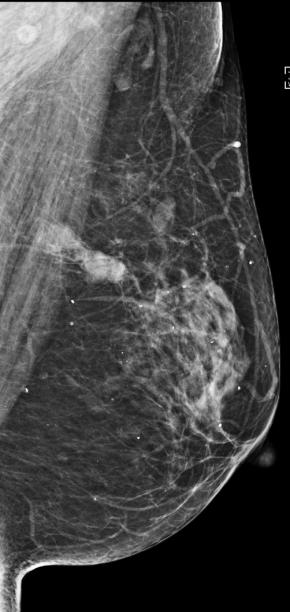

Diagnostic performance of the modified Korean Thyroid Imaging Reporting and Data System for thyroid malignancy according to nodule size: a comparison with five society guidelines

Dong Gyu Na, Wooyul Paik, Jaehyung Cha, Hye Yun Gwon, Suh Young Kim, Roh-Eul Yoo